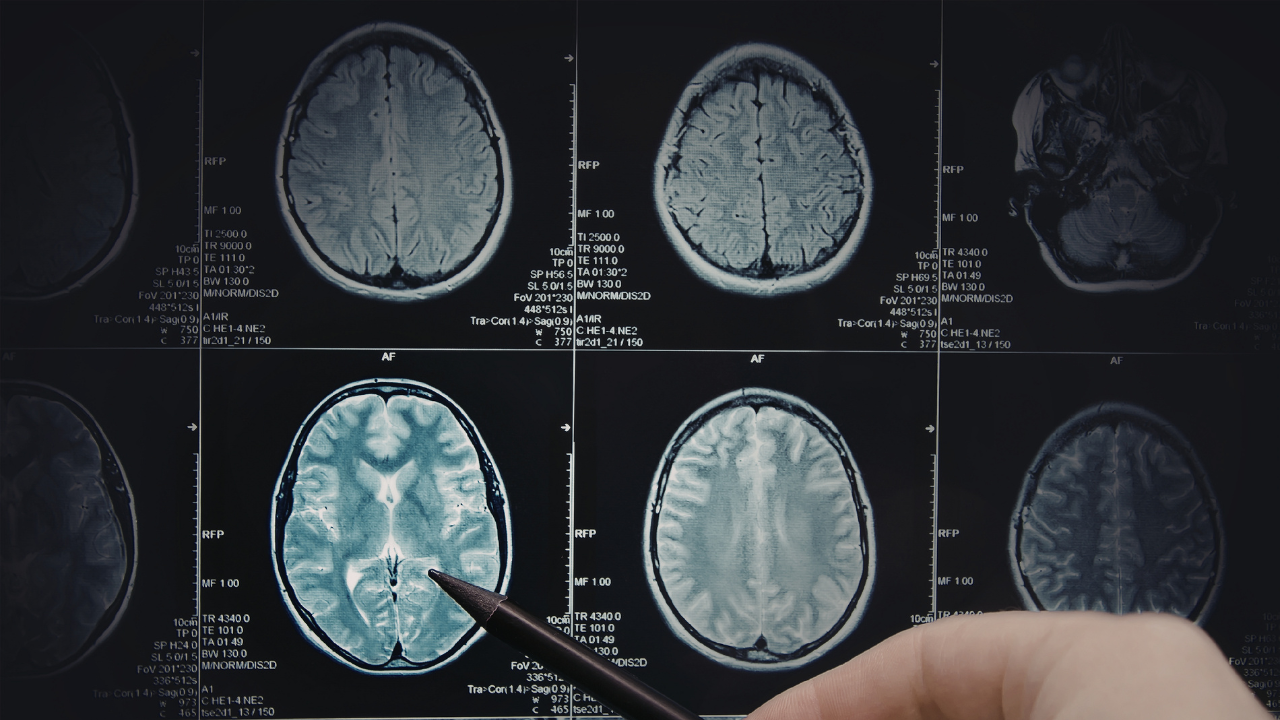

Adjuvant Temozolomide Improves Survival in 1p / 19q Non - Co - Deleted Glioma

In a significant development that has captured widespread attention, Adjuvant Temozolomide Improves Survival in 1p / 19q Non - Co - Deleted Glioma. This story represents a pivotal moment that analysts and observers have been closely monitoring. The implications of this news extend far beyond the immediate headlines, touching on broader themes that resonate with audiences across United States and beyond.